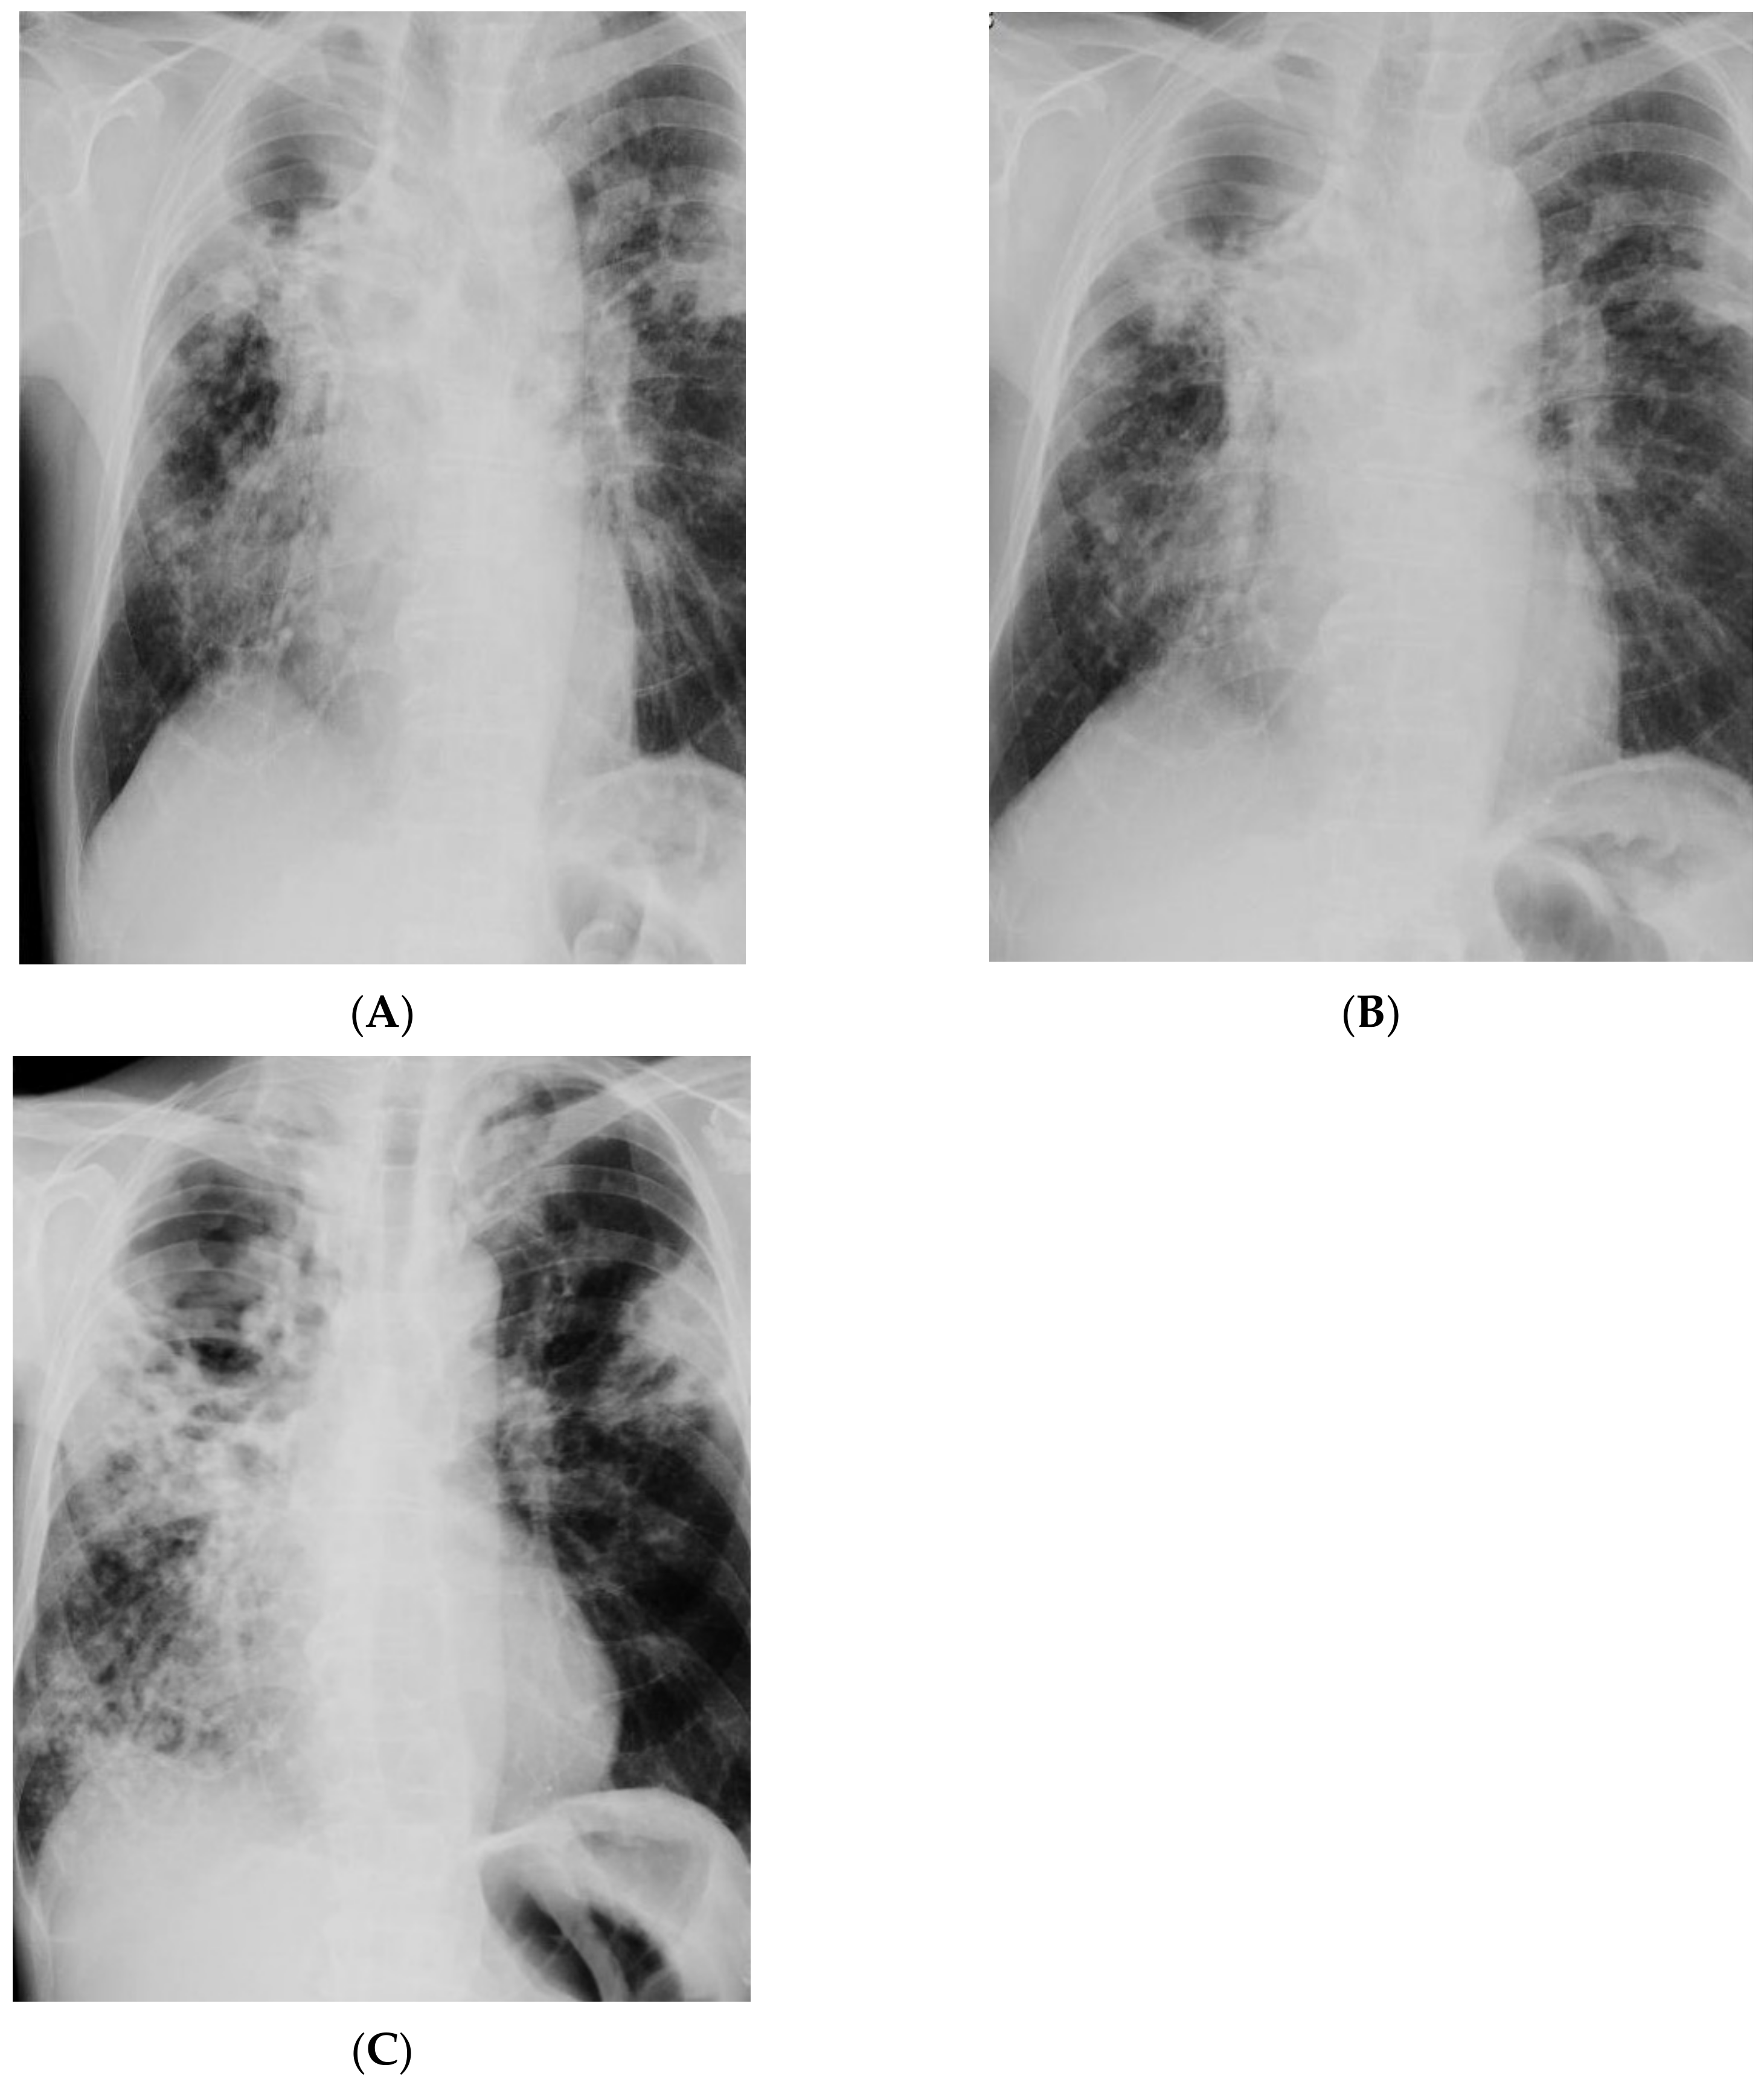

| Imaging studies | Chest CT: Lesions in the lungs (cavities and nodules), enlarged mediastinal lymph nodes, 2 abscesses in the subcutaneous tissue in the right supraclavicular area | Chest X-ray: Extensive bilateral infiltrative lesions, large cavity in the upper area of the right lung (Figure 5A) |

| Imaging studies during antimycobacterial treatment | Chest X-ray: After 2 mo of treatment—an irregular infiltration in the upper area of the right lung (Figure 2A). After 5 mo of treatment—reduced infiltration (Figure 2B) Chest CT: After 5 mo of treatment an oval nodular lesion with calcification, enlarged right and left mediastinal nodes, nodular lesions in the lungs (Figure 3A,B) | Chest X-ray: No improvement by radiographic criteria after 17 mo of treatment (Figure 5B). Still no improvement by radiographic criteria after further 2 years of treatment (Figure 5C) Chest CT: An extensive cavity in the upper lobe of the right lung, infiltrative lesions in the middle lobe, cavernous lesions in the left lung (Figure 4) |